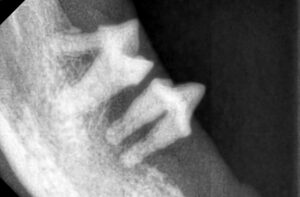

全身麻酔下で歯科レントゲンと歯周ポケットの測定(プロービング)などを行います。

これらの検査により、表面からは見えない顎の骨や歯根の状態を把握できます。

今回の歯科レントゲンでは、歯を支える顎の骨(歯槽骨)が重度に失われ歯根の周囲が露出している状態でした。

この状態になると歯垢・歯石を取り除くだけでは改善が難しく、ご家族と相談の上で抜歯を主体とした治療を行うこととなりました。